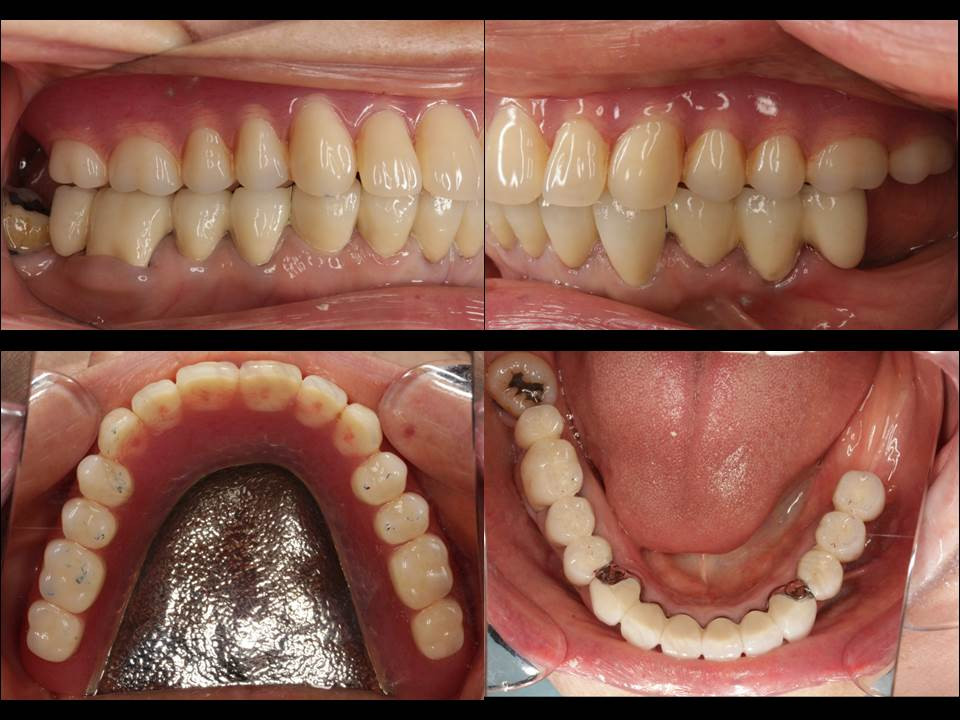

術後のお口の中の様子①

「咬合平面」といって、歯の咬む面の高さを適切に設定することで、噛み切った食べ物が頬側と舌側に流れる方向を正しくすることができ、舌痛お口の中の粘膜の痛みを改善することもあります。画像は術後の写真ですが、横から見ても、噛む面から上下を見ても、歯並びが正しく整っているのが分かると思います。

上顎は奥歯に1本だけ残っている歯を茶筒式の入れ歯であるレジリエンツテレスコープを、下顎は歯の動きを考慮した設計で Key&Key way 加工を施したブリッジで治療致しました。いずれもハイブリッドセラミックスによる治療となります。